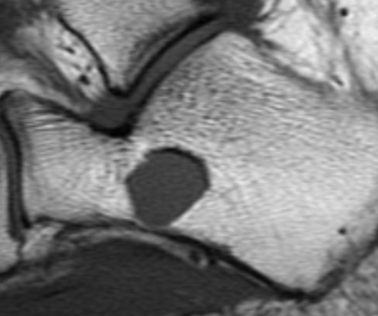

IRM

- Signal Kystique HyperT2 HypoT1

- Possible niveau si hémorragie

Localisation Calcanéenne Typique